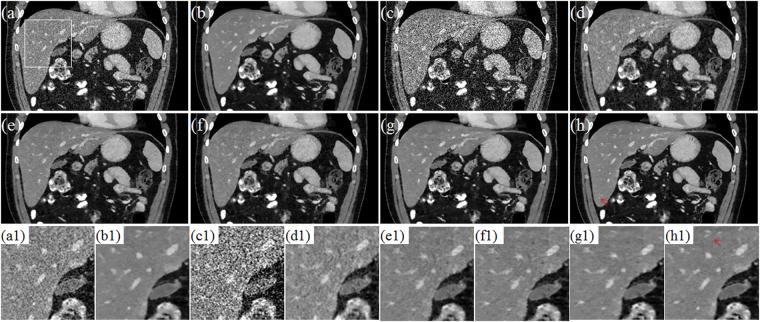

X-ray computed tomography (CT) has been widely used to provide patient-specific anatomical information in the forms of tissue attenuation. However, the cumulative radiation induced in CT scan has raised extensive concerns in recently years. How to maintain reconstruction image quality is a major challenge for low-dose CT (LDCT) imaging. Generally, LDCT imaging can be greatly improved by incorporating prior knowledge in some specific forms. A joint estimation framework termed discriminative prior-prior image constrained compressed sensing (DP-PICCS) reconstruction is proposed in this paper. This DP-PICCS algorithm utilizes discriminative prior knowledge via two feature dictionary constraints which built on atoms from the samples of tissue attenuation feature patches and noise-artifacts residual feature patches, respectively. Also, the prior image construction relies on a discriminative feature representation (DFR) processing by two feature dictionary. Its comparison to other competing methods through experiments on low-dose projections acquired from torso phantom simulation study and clinical abdomen study demonstrated that the DP-PICCS method achieved promising improvement in terms of the effectively-suppressed noise and the well-retained structures.

X 射线计算机断层扫描(CT)已广泛用于提供组织衰减形式的患者特定解剖信息。然而,近年来 CT 扫描引起的累积辐射引起了广泛关注。如何在保持重建图像质量是低剂量 CT(LDCT)成像的主要挑战。通常,可以通过以某些特定形式合并先验知识来大大改善 LDCT 成像。本文提出了一种称为鉴别先验-先验图像约束压缩感知(DP-PICCS)重建的联合估计框架。该 DP-PICCS 算法通过分别基于组织衰减特征补丁和噪声-伪影残差特征补丁的样本的原子构建的两个特征字典约束来利用鉴别先验知识。此外,通过对来自体模模拟研究和临床腹部研究的低剂量投影的实验,先验图像的构建依赖于两个特征字典的鉴别特征表示(DFR)处理。通过与其他竞争方法的比较,DP-PICCS 方法在有效抑制噪声和保留结构方面取得了有希望的改进。